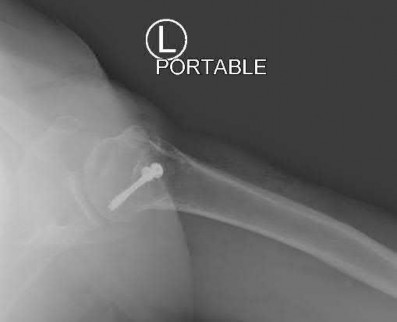

A 55-year-old patient presents with a slowly enlarging, painful mass in the proximal humerus.

Biopsy reveals a hyaline cartilage matrix with cellular atypia, confirming a diagnosis of central conventional chondrosarcoma. Which of the following genetic mutations is most frequently identified in this specific tumor?

Explanation

Mutations in the isocitrate dehydrogenase genes, IDH1 and IDH2, are found in up to 50-60% of central conventional chondrosarcomas and enchondromas. EXT1 and EXT2 mutations are characteristic of multiple hereditary exostoses (osteochondromas). GNAS mutations are seen in fibrous dysplasia. TP53 and RB1 mutations are hallmark aberrations in osteosarcoma.